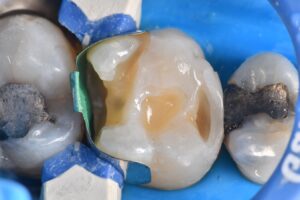

CONVERSION to a CLASS I

// Localized treatment of this first molar pre-Christmas due to mechanical discomfort when flossing on the mesial aspect secondary to an enamel fracture overlying caries. The treatment plan involved all three teeth, but as Christmas would have it, let’s break it up =)